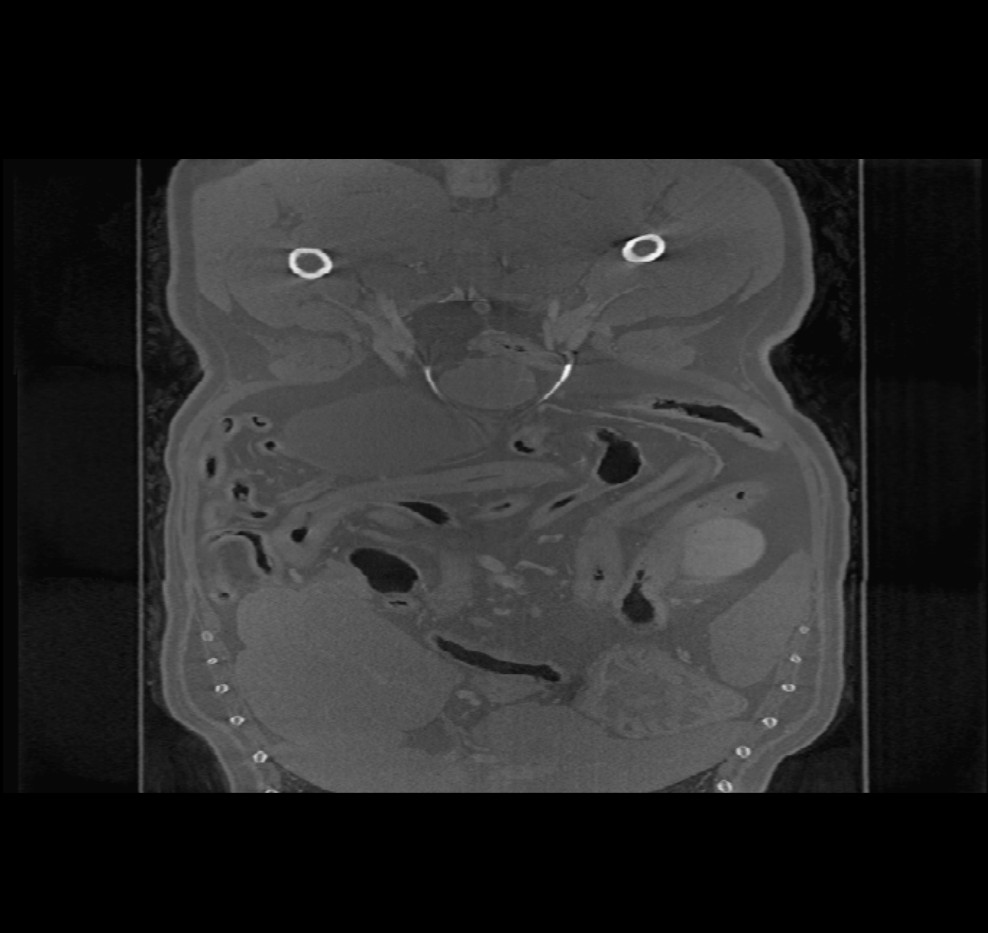

Beim Öffnen volumetrischer DICOM-Bilder im Viewer (CT- und MR-Modus) steht in der oberen Symbolleiste ein zusätzliches Menü mit dem Titel Bildebenen zur Verfügung. Ändern Sie die Ausrichtung des Bildes, indem Sie eine der drei verfügbaren Ebenen auswählen (Axial, Koronal und Sagittal).

Die gewählte Ebene beeinflusst die Position und Ausrichtung der CT-/MR-Schnitte sowie deren Rekonstruktion auf der 2D-Ebene.